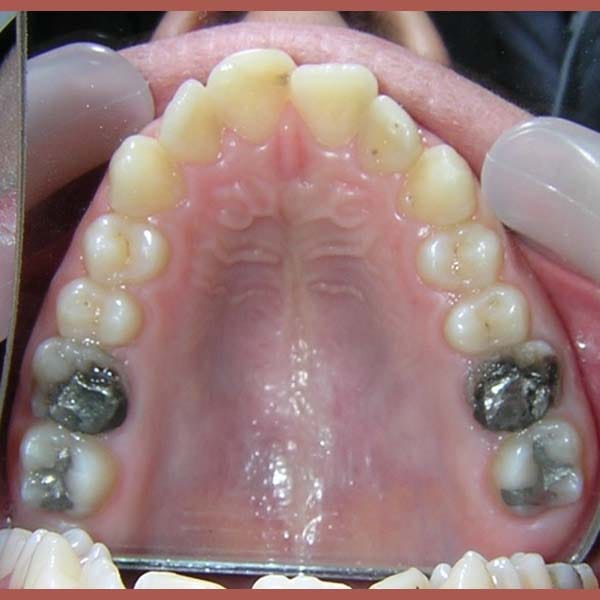

BEFORE

This young man visited me due to the severe protrusion in his teeth. Upon examination, I noticed the presence of molars with large fillings, which are not expected to endure for a long time.

So we decided to extract these two molars and use their space to return the front teeth back, in the end, our friend regained his beautiful smile again.